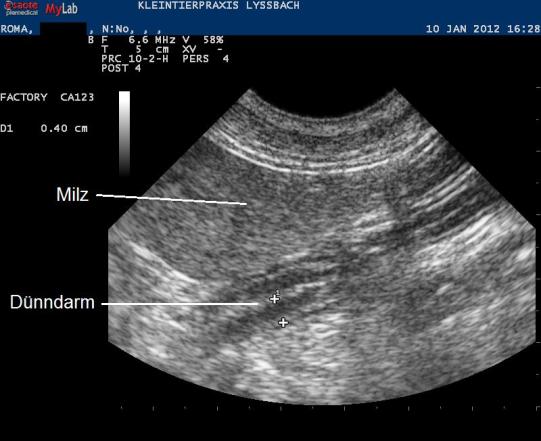

Eine Blutuntersuch zeigt keine Hinweise auf Veränderungen der inneren Organe wie Leber und Nieren, auch die Bauchspeicheldrüse scheint nicht entzündet zu sein. Die Nebenniere zeigt im Test eine normale Funktion, und ein Ultraschall der Bauchhöhle fördert keine Auffälligkeiten zutage - der Darm erscheint durchgängig, Darm- und Magenschleimhaut sind nicht verdickt, auch werden keine Hinweise für ein Magengeschwür gefunden. Auch eine Entwurmung verbessert das Problem nicht.